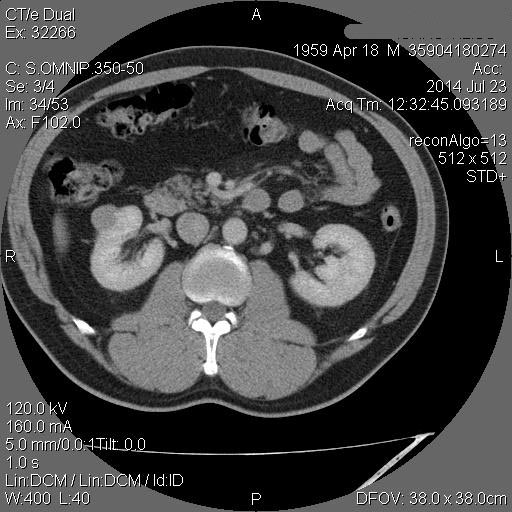

Образование в правой почке

Мужчина средних лет.Жалоб не предъявляет.

С его слов, 10 лет назад в правой почке находили кисту.

Рак - на первом месте. Показано КТ с контрастирванием.

Ответ каунасских радиологов - киста почки.

В том то и дело. Но тем не менее - это киста, анамнез уже несколько лет.besliu писал(а):Что-то на узи на кисту не похоже...

Динамики нет, на последнем видео четко видна киста при включенной 2й гармонике